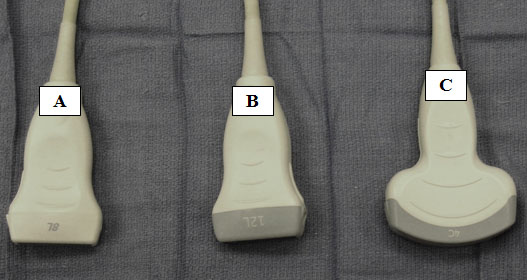

The transducers needed for the visualization of axial structures include linear and curved array transducers (Figure 1).[2] The linear transducers assist in the visualization of superficial structures including nerves and blood vessels with small diameters. High-frequency linear transducers provide better resolution but offer less penetration. The use of linear array transducers in the cervical spine region allow for visualization of cervical medial branches, nerve roots, and some critical vascular structures.

Curved array transducers allow for the delineation of a greater region and for the visualization of deeper structures. Curved array transducers are utilized for lumbosacral spine ultrasound.

Figure 1. Medium (A) and high frequency (B) linear transducers. Low frequency curvilinear array transducer (C).